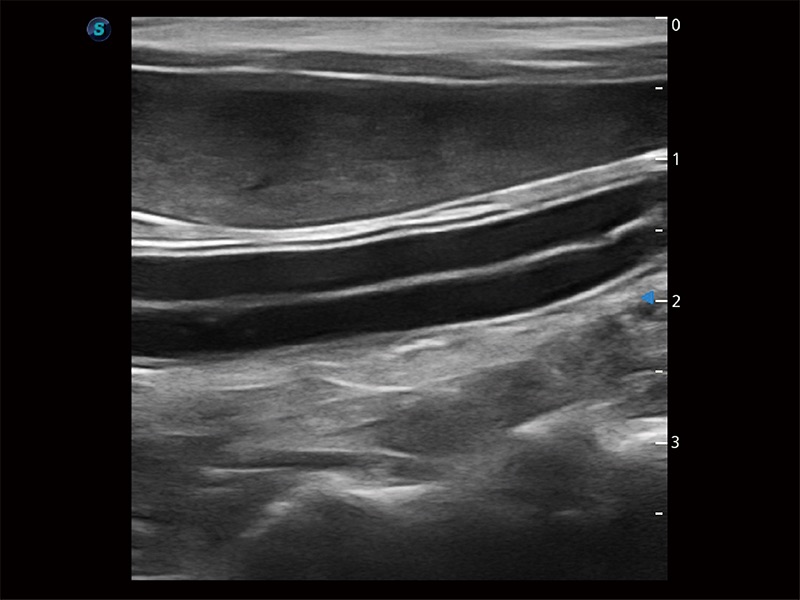

优异的基础图像

ProPet 80 全新的动物超声智能软件和丰富的探头群,为动物医生提供了高清晰度和精细分辨率的图像,无论在宠物、马科、畜牧还是实验室动物等应用中都可以轻松应对,为您的日常工作带来满意的体验。

(犬)肠道